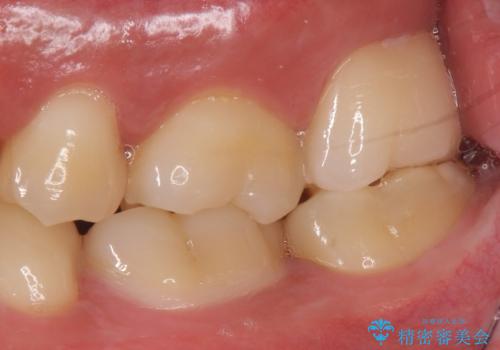

- 銀の詰め物のやり替えを主訴に来院されました。

歯の奥が歯ぐきに埋もれている状態であったため、埋まっている親知らずを抜歯しつつ歯茎の高さを落とし、外れにくいジルコニアクラウンを装着していきます。

- 左上7 歯肉切除:5,500円/仮歯:11,000円/ジルコニアクラウン:110,000円費用は治療当時の料金となります

歯のみでなく歯茎の調整も行うことで、外れにくい被せ物を装着することが可能になります。